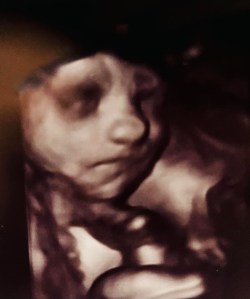

More than one family member has recently found themselves in the hospital for scans. One of Sarah’s routine check-ups confirmed that her baby is a boy and produced an incredible set of photographs. Isn’t modern technology marvellous?